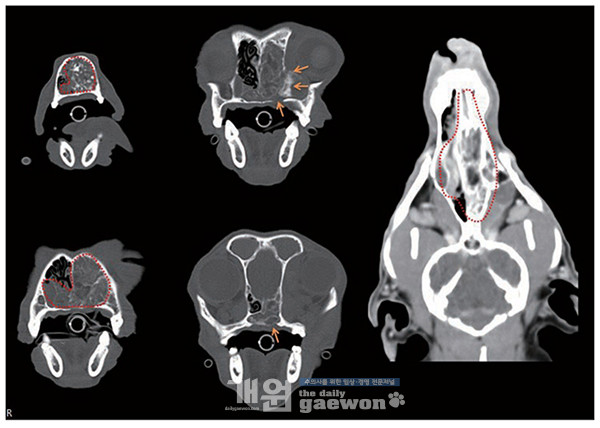

본원에서 CT 재촬영 및 비강 색전술이 계획되었다. CT 영상에서 비강 종괴는 좌측 비강을 가득 채울 뿐만 아니라 우측 비강 일부, 비인두까지 확장되어 있었으며, 종괴 주변의 상악골의 bone lysis 및 골 증식성 병변도 동반되어 있었다[그림 2]. 이전의 조직검사와 본원 CT 재촬영 영상의학적 특징을 모두 고려할 때 nasal angiofibroma가 가장 의심되었다.